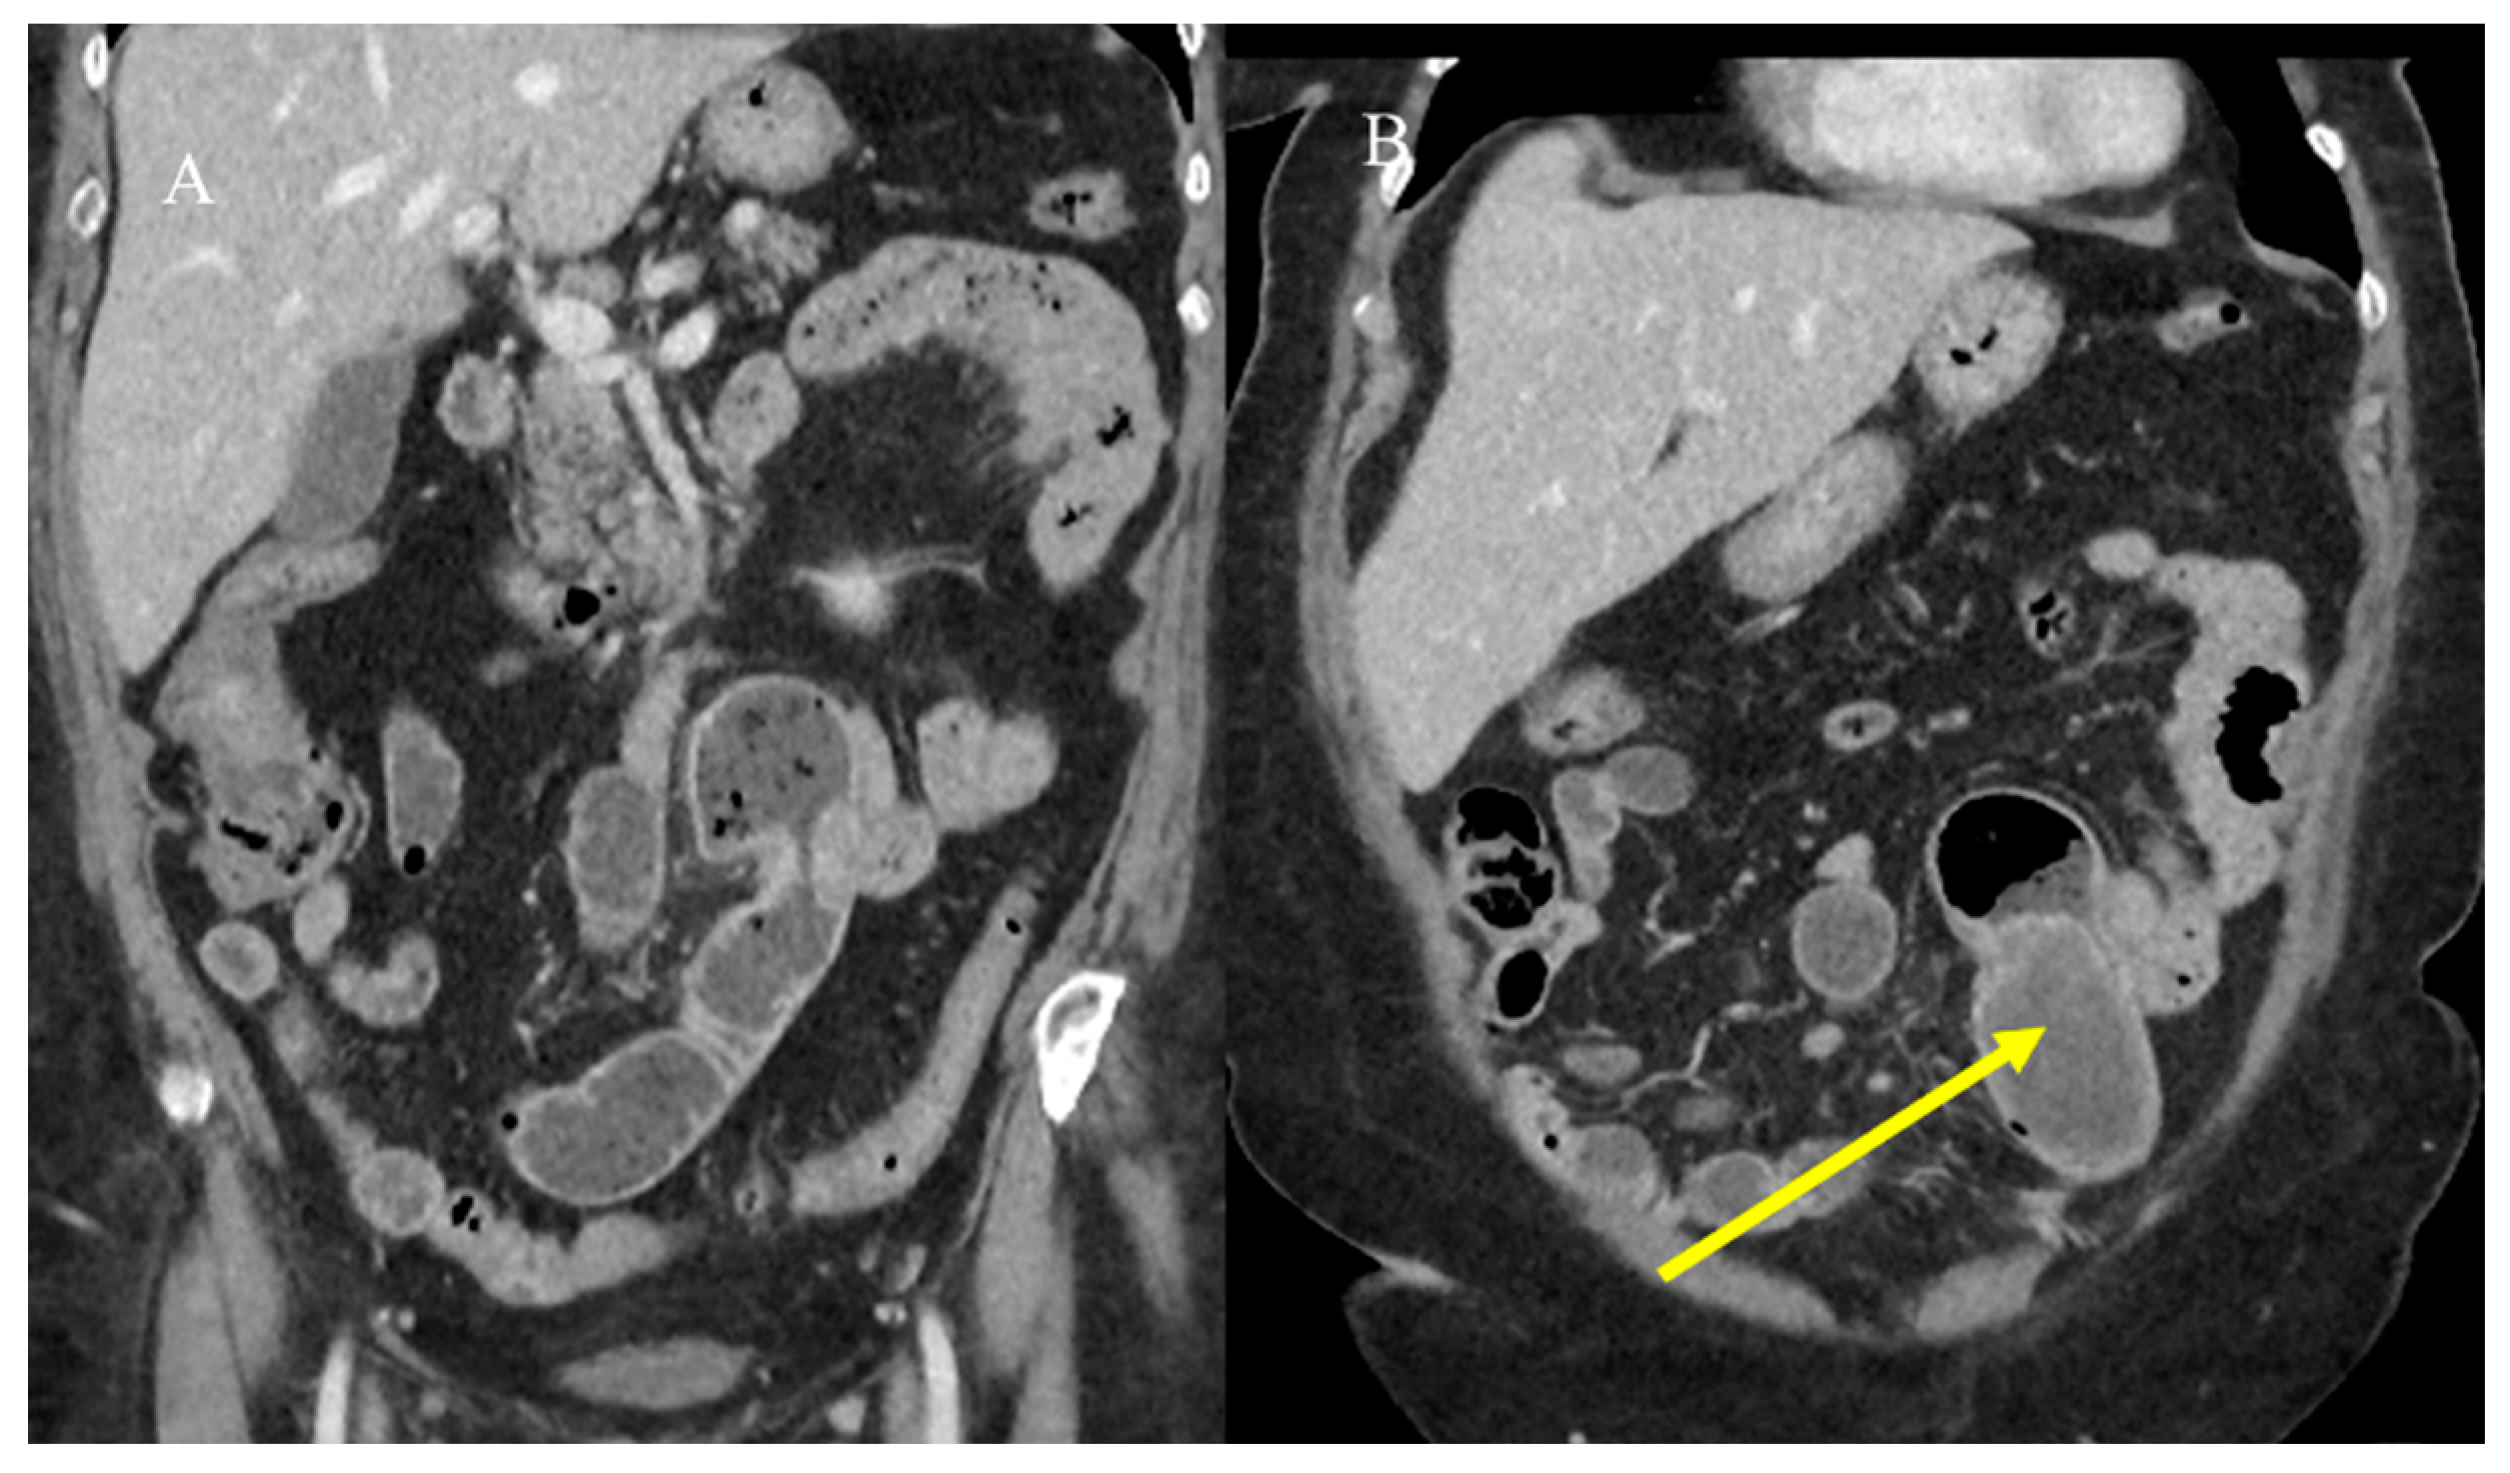

2.7. Metastatic Presentation of Small Bowel Tumors

- Attiyeh, M.A.; Malhotra, G.K.; Li, D.; Manoukian, S.B.; Motarjem, P.M.; Singh, G. Defining MRI Superiority over CT for Colorectal and Neuroendocrine Liver Metastases. Cancers 2023, 15, 5109. [Google Scholar] [CrossRef]

- Shenoy-Bhangle, A.; Baliyan, V.; Kordbacheh, H.; Guimaraes, A.R.; Kambadakone, A. Diffusion weighted magnetic resonance imaging of liver: Principles, clinical applications and recent updates. World J. Hepatol. 2017, 9, 1081. [Google Scholar] [CrossRef]